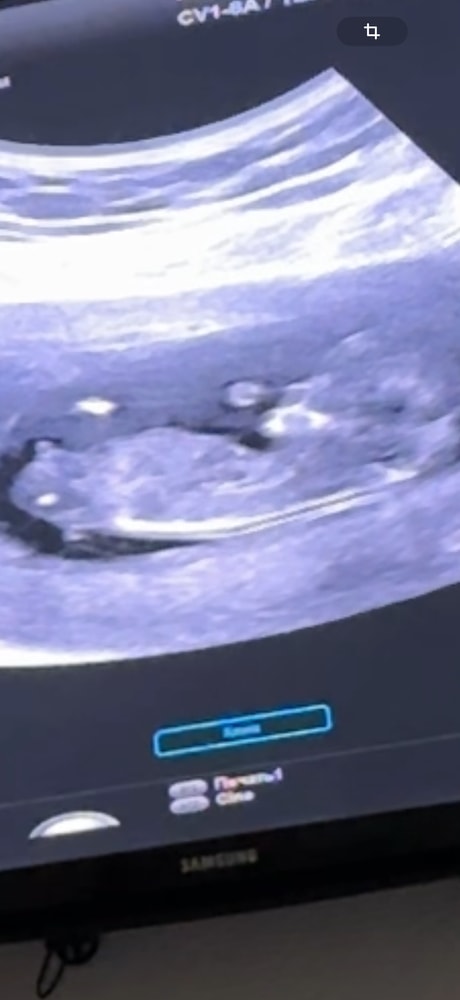

Какой пол вы тут видите ?

Да там писюн огромный, конечно мальчик

Александра, ну или если срок маленький и это половой бугорок, то тоже мальчуковый

100 мальчишка у вас

Мальчик

11+5 фото узи Доплер